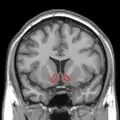

MRI coronal slice showing nucleus accumbens outlined in red MRI coronal slice showing nucleus accumbens outlined in red